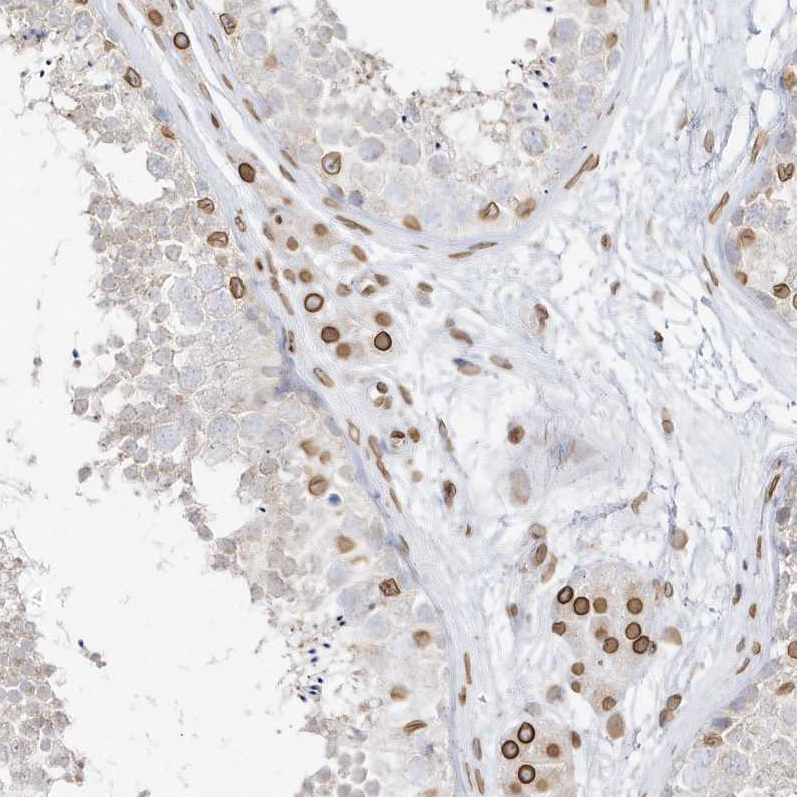

Immunohistochemical staining of human testis shows strong positivity in nuclear membrane in Leydig cells and a subset of cells in seminiferous ducts.